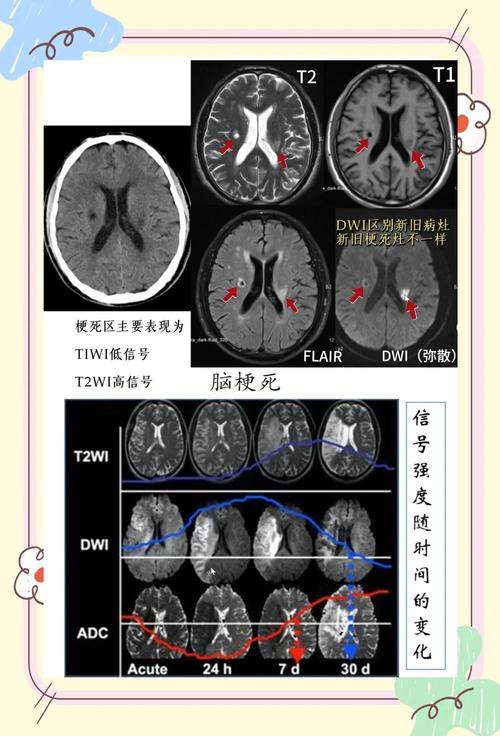

| CT影像表现 | 发病早期(6小时内)可能正常,6小时后逐渐出现低密度灶,边界不清,可伴有占位效应(脑组织水肿,导致中线移位)。 | 急性期可能看不到或仅表现为一个微小的、边界清晰的低密度灶。 慢性期表现为一个边界清晰、圆形或卵圆形的小低密度灶,无占位效应。 |

CT的局限性:

(图片来源网络,侵删)- 对于超早期的脑梗(<6小时),CT可能完全正常,此时需要更敏感的MRI(磁共振),特别是DWI序列来发现病灶。

- 对于非常新鲜的、极小的腔梗,CT可能也看不清,MRI对微小病灶的显示能力远优于CT。